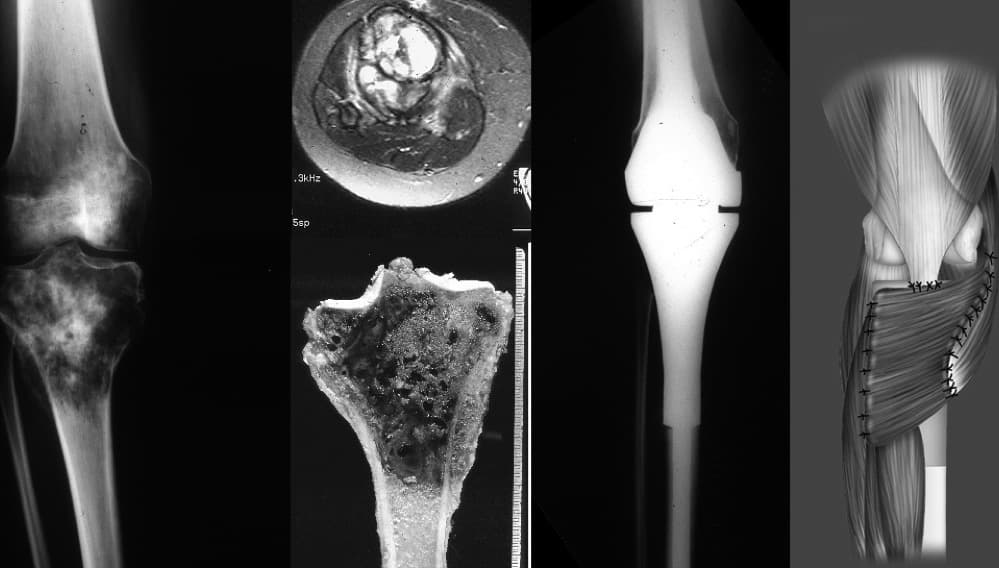

vignette|Ostéosarcome d'un animal à un stade avancé. Un ostéosarcome (sarcome ostéogène) est la plus courante des tumeurs malignes osseuses primaires, si l'on exclut les myélomes et les lymphomes. Il a une prédilection pour la région des métaphyses des os longs tubulaires. 50 % des cas se produisent autour du genou. Il s'agit d'une tumeur maligne d'origine osseuse (ostéoblastes) dont les cellules néoplasiques forment du tissu osseux tumoral (parfois mélangé à du tissu chondrale tumorale). Cette forme de cancer est toujours considérée comme rare. À ne pas confondre avec un fibrosarcome ou un chondrosarcome. On la différencie de l'ostéome et de l'ostéoblastome par son caractère évolutif et son envahissement important des tissus mous adjacents, associé à une rupture de la corticale de l'os. D'où sa malignité. Entrainant selon les cas, des conflits articulaires et/ou tendineux, ainsi que des compressions vasculaires et/ou nerveuses. L'ostéosarcome est la huitième forme la plus courante de cancer chez les enfants, comprenant 2,4 % de toutes les tumeurs malignes chez les patients pédiatriques, et environ 20 % de tous les cancers des os primaires. L'incidence de l'ostéosarcome est estimée à 5 cas par million d'habitants par an pour la population américaine, avec une légère variation entre les individus d'ethnies noires, hispaniques et blanches (respectivement 6,8, 6,5 et 4,6 de cas par million de personnes et par an). C'est légèrement plus fréquent chez les hommes (5,4 par million par an) que chez les femmes (4,0 par million par an). Elle provient le plus souvent dans la région métaphysaire des os longs tubulaires, avec 42 % se produisant dans le fémur, 19 % dans le tibia et 10 % dans l'humérus. Environ 8 % des cas surviennent dans le crâne et la mâchoire, et 8 % dans le bassin. L'ostéosarcome est le sixième cancer le plus fréquent chez les enfants de moins de 15 ans. Il affecte 400 enfants de moins de 20 ans et 500 adultes (la plupart entre 15 et 30 ans) chaque année aux États-Unis. Environ 300 des 900 personnes meurent chaque année.